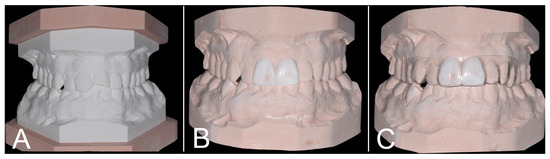

2. Case Report